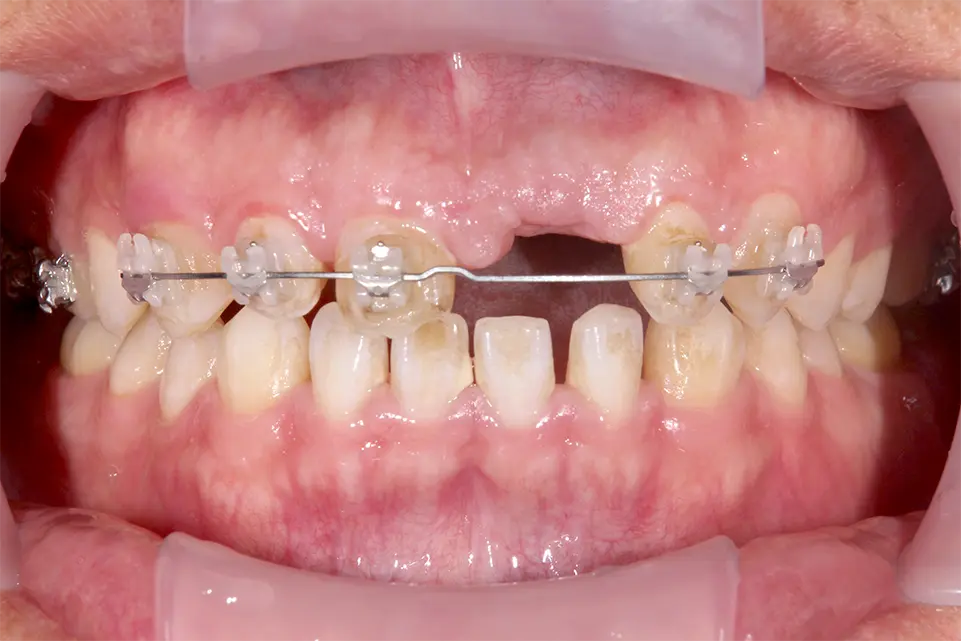

矯正治療

| 治療方法 | レントゲンで精査すると歯根が破折しており保存不可能なので抜歯。 もともと正中離開し審美的にも不良であった。正中離開した状態でそのまま治すのかこの際、審美的にも改善したいのか2つのオプションを提示すると矯正治療をした上で完璧に治したいとの要望があったので矯正治療を行いインプラント治療する計画を立てた。両隣在歯3本はジルコニアセラミック審美治療を行った。 |